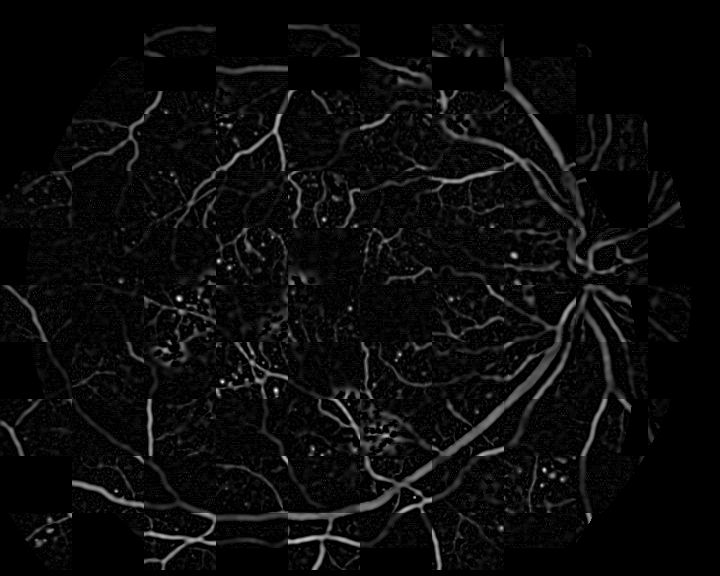

where m=1𝑚1m=1 for the angiography and m=1𝑚1m=-1 for the retinography, and subscript\lceil\cdot\rceil_{\emptyset} denotes the halfwave rectification. The rectification is used to avoid the negative Laplacian peaks outside the vessel regions so that only the vessel interiors are represented in the enhanced images. This results in a common representation for the retinography and the angiography, with enhanced vessel regions and the same intensity level pattern. Figure. 2 shows the result of the vessel enhancement operation applied to the retinography/angiography pair exposed in Fig. 1.

Refer to caption

Figure 2: Examples of the vessel enhancement operation applied to the multimodal image pair in Fig. 1: (a) result from retinography; (b) result from angiography.